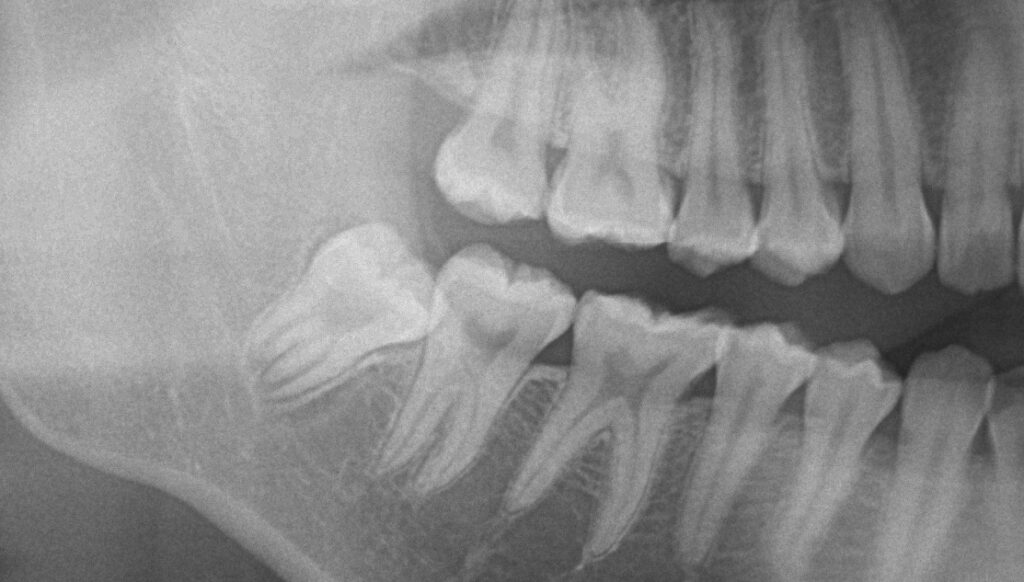

以下の二つの完全に埋まってる親知らず簡単に抜けます。